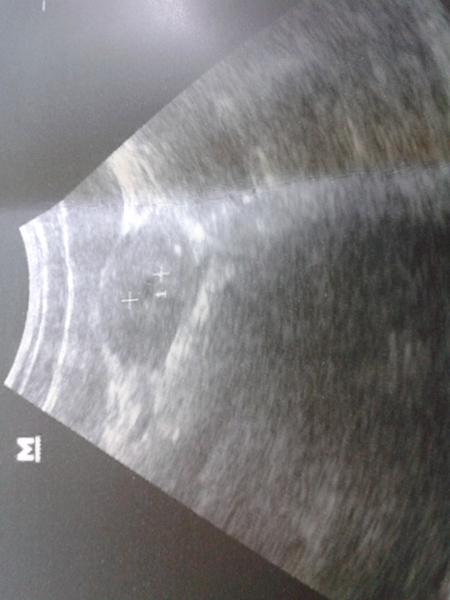

to já jsem byla v sobotu na pohotovosti protože jsem začala trochu krvácet ale nebyla to uplne krev ale jako by zředěná krev spíš voda obarvená no ale abych se dostala k jádru věci dostala jsem léky na zklidněni dělohy měla jsem ji podrážděnou a jsem v 6 tt a 3 dny a naše fazolka měří 5,8 mm takže celkem veliká fazolka moje